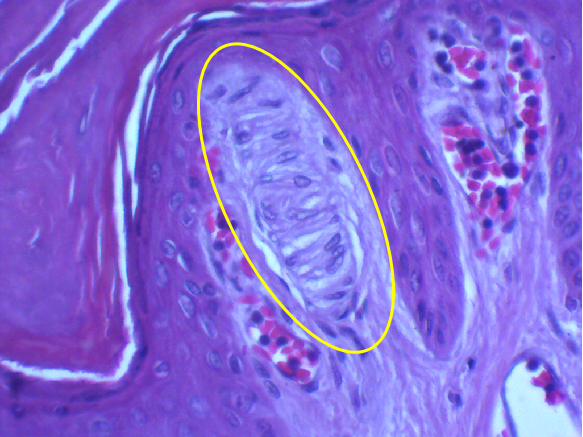

图6 触觉小体光镜图 (HE染色)